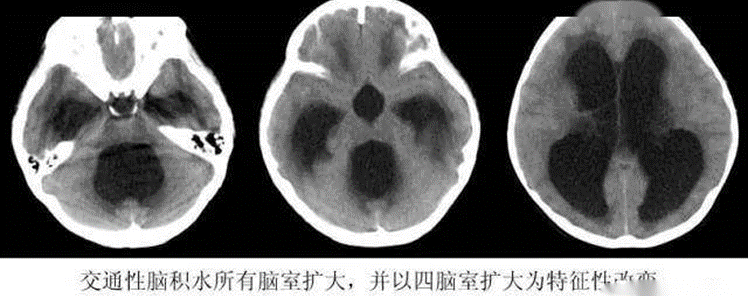

图1 脑积水影像学图示意

学生可通过鼠标和键盘操作,自由进入到 3D 虚拟的手术室,点开某个患者的病史及影像学,进行影像读片,选择是否需要手术干预。(此点考查脑室引流的适应症、禁忌症。)